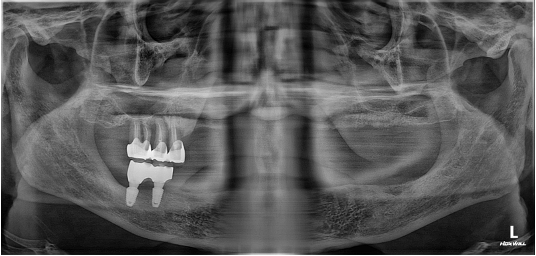

디지털 풀아치 임플란트(상악) & 전체 임플란트(하악) (64세 여성)